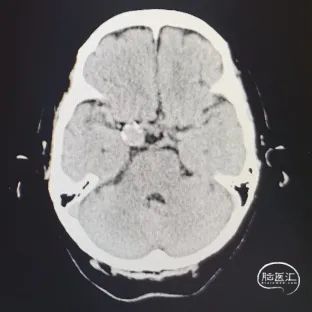

头痛2天。2021-09-19外院CT提示右鞍旁类圆形稍高密度影。

图2 头颅CTA提示右颈内海绵窦段动脉瘤,基底动脉中段重度狭窄。

右颈内动脉海绵窦段起始部类圆形瘤样扩张,最大约19mm╳14mm,瘤颈约14mm,基底动脉中段重度狭窄。